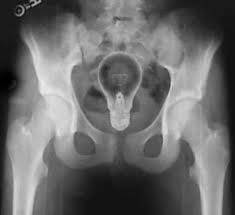

Physicians use nuclear medicine techniques such as SPECT scans to observe how the heart pumps, follow patterns of blood flow, and identify diseases that are otherwise hidden deep within the body. Current scanners, however, rely on detectors that are both costly and difficult to manufacture.

Nuclear medicine techniques such as SPECT (single-photon emission computing tomography) function like an invisible camera. A physician introduces a small, safe, and short-lived radiotracer into a targeted area of the patient’s body. This tracer releases gamma rays, which travel through tissues and are then captured by a detector outside the body. Each gamma ray acts like a pixel of light, and when millions of these pixels are recorded, computers assemble them into a three-dimensional image of organ activity.